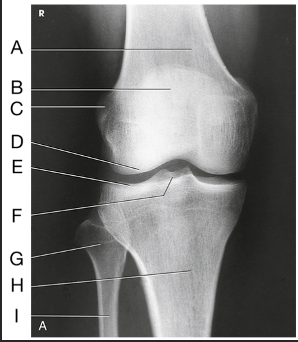

Name this projection.

AP axial IC Fossa

Name the method used.

Béclére Method

How do you know this image is a Beclere Method

Marker (line yourself up... only AP IC fossa) and is the smallest unilateral IC fossa (not elongated like Camp-Coventry and not as big as Holmblad)

Label the image: A

femur

Label the image: B

lateral condyle

Label the image: C

intercondylar fossa

Label the image: D

medial condyle

Label the image: E

intercondylar eminence

Label the image: F

tibia

Label the image: G

fibula

How does the IC fossa appear in the AP axial projection compared to the PA axial projection? (What sets the Beclere apart from the Holmblad/Camp-Coventry images?)

In Merrill's, the Beclere method makes the IC fossa look smaller. However, because we no longer have 10x12cassettes, we are forced clinically to have a larger OID in the AP axial projection, making the image look magnified compared to the PA axial projections

What are all three projections of the IC fossa looking for?

An open IC fossa (where the patellar apex is not superimposing the fossa)